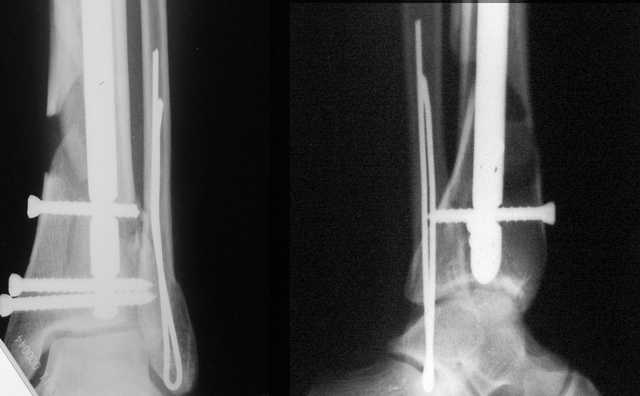

A propos fibular fixation if one is eager to stabilize it separately. In the fracture pattern a way of closed fixation by V-shaped stressed wire (advanced by colleagues from Moscow, prof. Lazarev A.F. et al.) must be excellent. We use indirect closed reduction by the external fixator. Example attached, that fibular fracture is even more suitable for plating but the wire did the job.

Второй случай сделан из одного разреза

Дж

Идея хорошая, особенно если короткий и поперечный перелом. Узнал о методе на прошлогодней конференции в Санкт Петербурге, доклад от ЦИТО,

и в доказательство Александр показал на своих снимках оригинальность метода, концепция "сделай сам имплант" из малого разреза и доступность. (при совершенствовании методики и инструментарии, метод может быть применен и в других случаях)